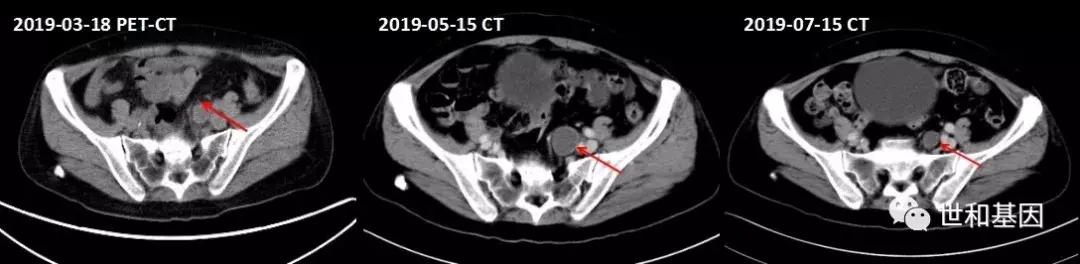

- 2019年4月,多西他赛100mgd1+安罗替尼8mgd1-14,21d/cycle,治疗4程,复查CT:腹股沟等处淋巴结明显缩小,疗效评价PR。

左:治疗前CT(双侧肾上腺区、腹主动脉旁多发转移淋巴结,红色箭头标记)

右:治疗后CT(转移灶明显缩小)